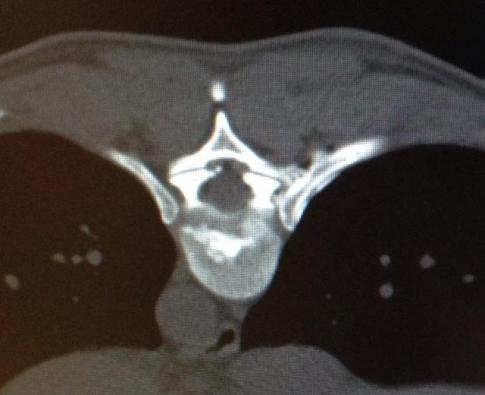

In lokaler Betäubung wird eine Laserfaser durch eine Punktionskanüle in die betroffene Bandscheibe eingeführt. Unter kontinuierlicher Röntgenkontrolle wird die Nadel millimetergenau platziert. Das Verfahren zählt zur Mikrotherapie und beruht auf der Schrumpfung von Bandscheibengewebe durch Hitze. Der innere Kern der Bandscheibe, der Nucleus pulposus, wird dabei schonend verkleinert. Ein Bandscheibenvorfall kann sich dadurch schneller zurückziehen. Es erfolgt eine rasche räumliche Entlastung der bedrängten Nervenwurzel. Weiterhin führt die Hitze zu einer Verödung der Schmerznerven, welche die Bandscheibe umgeben.

Hierbei wird unter Röntgenkontrolle eine dünne Nadel an die schmerzhaften Gelenke der Wirbelsäule geführt. Die anschließende Verödung der Nerven, welche die Schmerzen verursachen, erfolgt über eine Glasfaser.